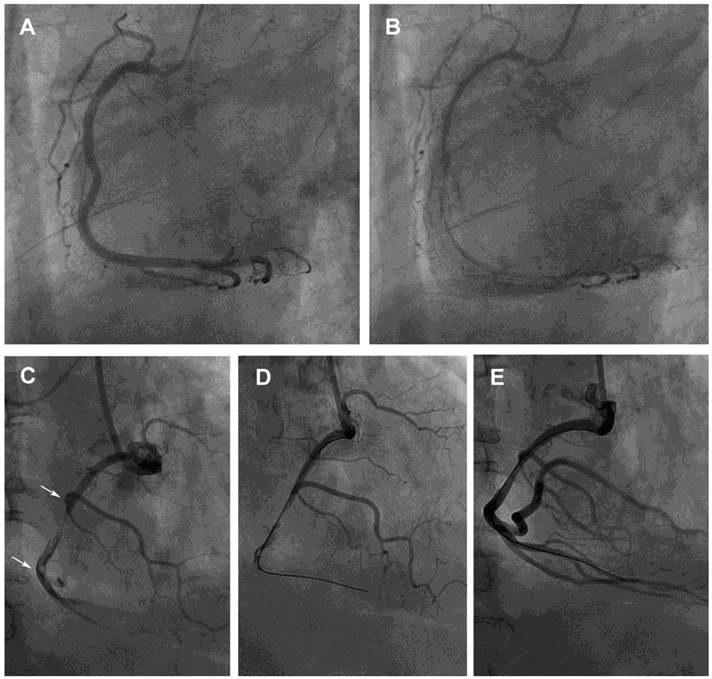

The mean age of the 869 patients who underwent diagnostic coronary angiography was 57±12 years, and 39% were women. A total of 495 patients had CAS (spasm group) (Figure 1) and 374 did not have CAS (control group). Advanced age, male gender, and current smoking status were associated with a greater likelihood of developing spasm. Moreover, Hb level, hematocrit, platelet count, and hs-CRP were significantly higher in the spasm group than in the control group (Table 1). Single-vessel spasm was the most common finding in patients with spasm, and spasm was provoked mostly in the right coronary artery. The number of patients who used β-blockers and calcium-channel blockers before coronary angiography was significantly greater in the control group than in the spasm group. However, after coronary angiography, the number of patients who used calcium-channel blockers and nitrates was significantly greater in the spasm group than in the control group.

Figure 1

Provoked coronary spasm and a dynamic interaction between platelet aggregates and spontaneous spasm related to angina and myocardial infarction, respectively. (A) A 62-year-old man had an unstable angina, presenting after wakening with resting chest tightness at night. Baseline angiography showed normal right coronary artery (RCA) with minimal plaquing. (B) Nearly 100% spasm appeared at middle and distal sites after intracoronary administration of 46 μg methylergonovine, which responded to intracoronary nitroglycerin 200 μg. (C) A 59-year-old man, a 15-cigarettes-per-day smoker, with a platelet count of 317×109/l had an acute inferior ST-segment elevation myocardial infarction. His platelet count was 264×109/l 1 year before this event. A subtotal occlusion without response to intracoronary nitroglycerin 400 μg with a large intramural thrombus in the mid-RCA (arrows) lead to poor distal runoff flow. (D and E) Manual thrombectomy using a Thrombuster catheter aspirated a large red thrombus clot about 1.5×20 mm. He then developed further chest pain and ST-segment elevation inferiorly. The mid RCA segment showed severe spasm with disappearance of mid and distal flow which responded to intracoronary nitroglycerin 200 μg. ST-segment elevation returned to baseline. He was then started on verapamil and aspirin and was asymptomatic at a 6 month follow-up.